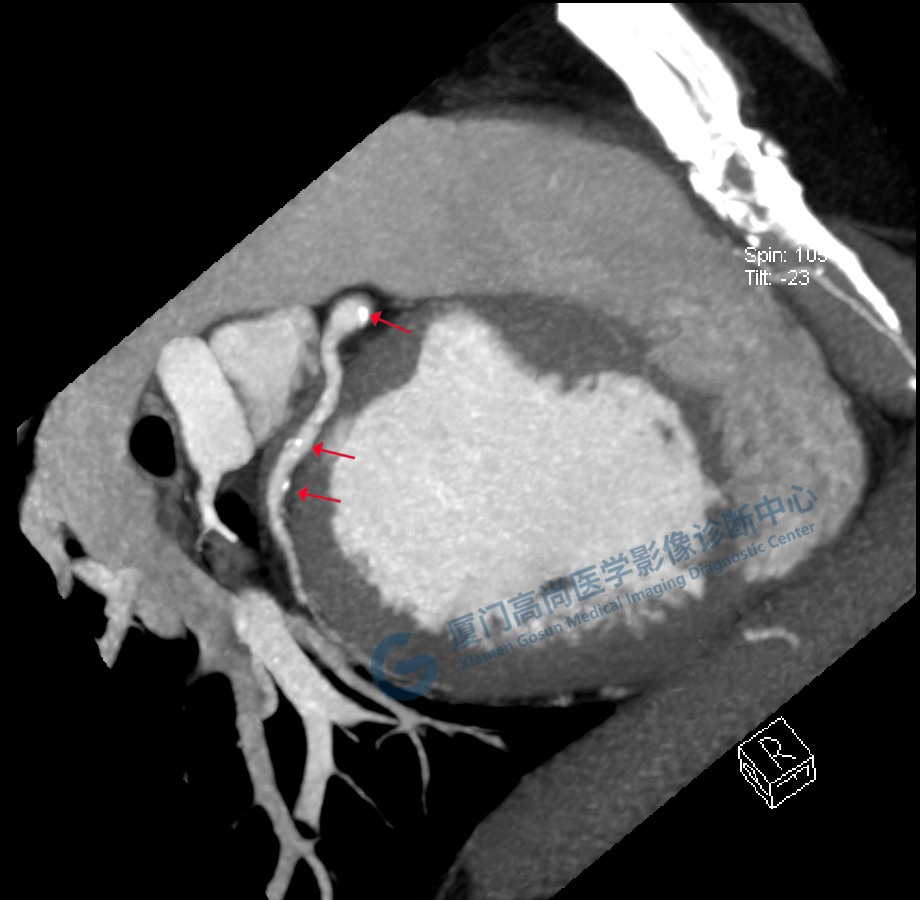

冠脈CTA圖像

冠狀CTA右冠

圖像所見(jiàn):左冠狀動(dòng)脈前降支,前降支近段可見(jiàn)局部鈣化斑塊,管腔狹窄約5%,左側(cè)冠狀動(dòng)脈對(duì)角支可見(jiàn)鈣化斑塊,管腔狹窄約20%-30%。

左冠狀動(dòng)脈回旋支,近段可見(jiàn)局部鈣化斑塊,管腔狹窄約5%-10%。

影像診斷:CAD-RADS分級(jí):2(25%-49%),輕度狹窄。